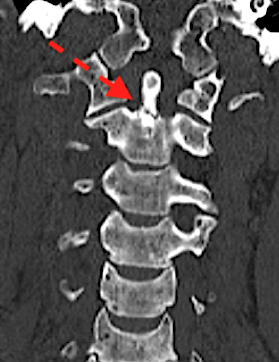

Sin embargo, la reconstrucción coronal del mismo paciente nos indica claramente que la fractura (flecha roja) se ubica en la base de la odontoides